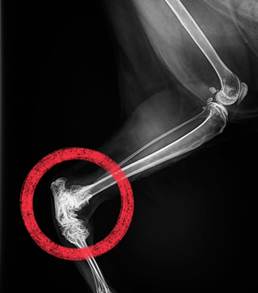

誤食、外傷、呼吸促迫、痙攣発作、血腹、尿閉など…患者の病態は数時間単位で変化するものから数日単位で変化するものまで様々です。その間の適切な処置によって患者のその後が左右される事は言うまでもありません。

当院では受付の段階でトリアージシステムを採用する事で、緊急症例に対してもより早急な対応に取り組めるよう努めております。

特に当院の院長(腫瘍科認定医)を始め、整形外科内科、循環器内科の専門外来も行っております。まずはご気軽にご相談ください。